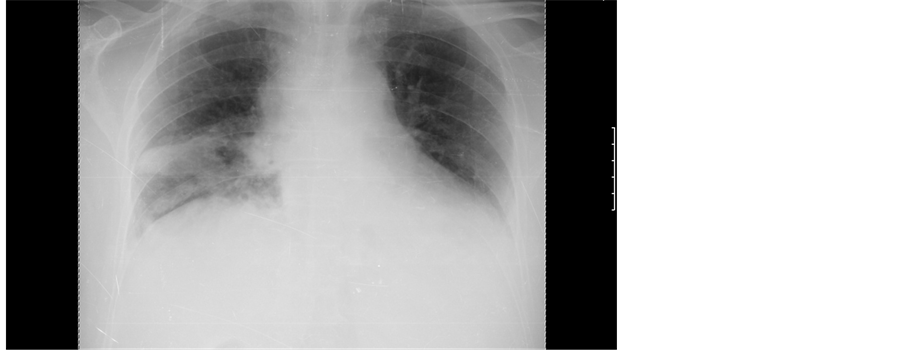

trophilia 80% and elevated CRP 11.5 mg/dL). Electrocardiogram presented with sinus tachycardia and low voltage. Chest radiograph revealed an increased cardiothoracic ratio, mediastinal widening and opacity in the middle lobe of the right lung (Figure 1).

Figure 1. Chest radiograph showed increased cardiothoracic ratio (>0.5), mediastinal widening, hypotransparent opacity in the middle right pulmonary lobe with dimensions of 41 × 28 mm and elevation of the right diaphragmatic dome.